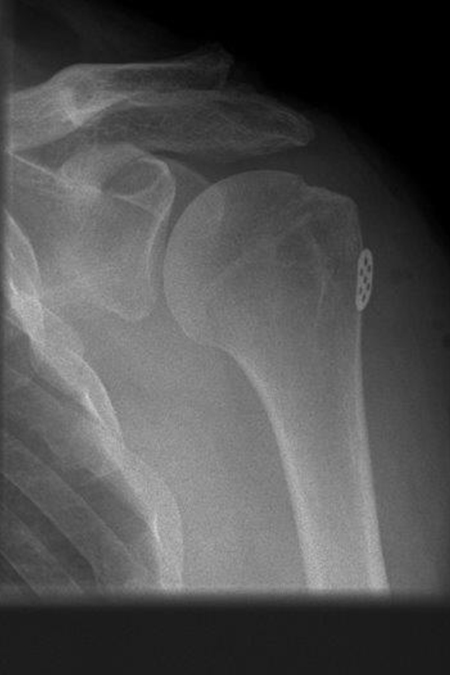

ROTATORENMANSCHETTENMASSENRUPTUR

Rotatorenmanschettemassenruptur: Subscapularis- und Infraspinatus-Abriss

Rotatorenmanschettemassenruptur: Supraspinatusabriss

Rotatorenmanschettemassenruptur: teils offene transossäre Auszugsnähte mit Fixation über Plättchen